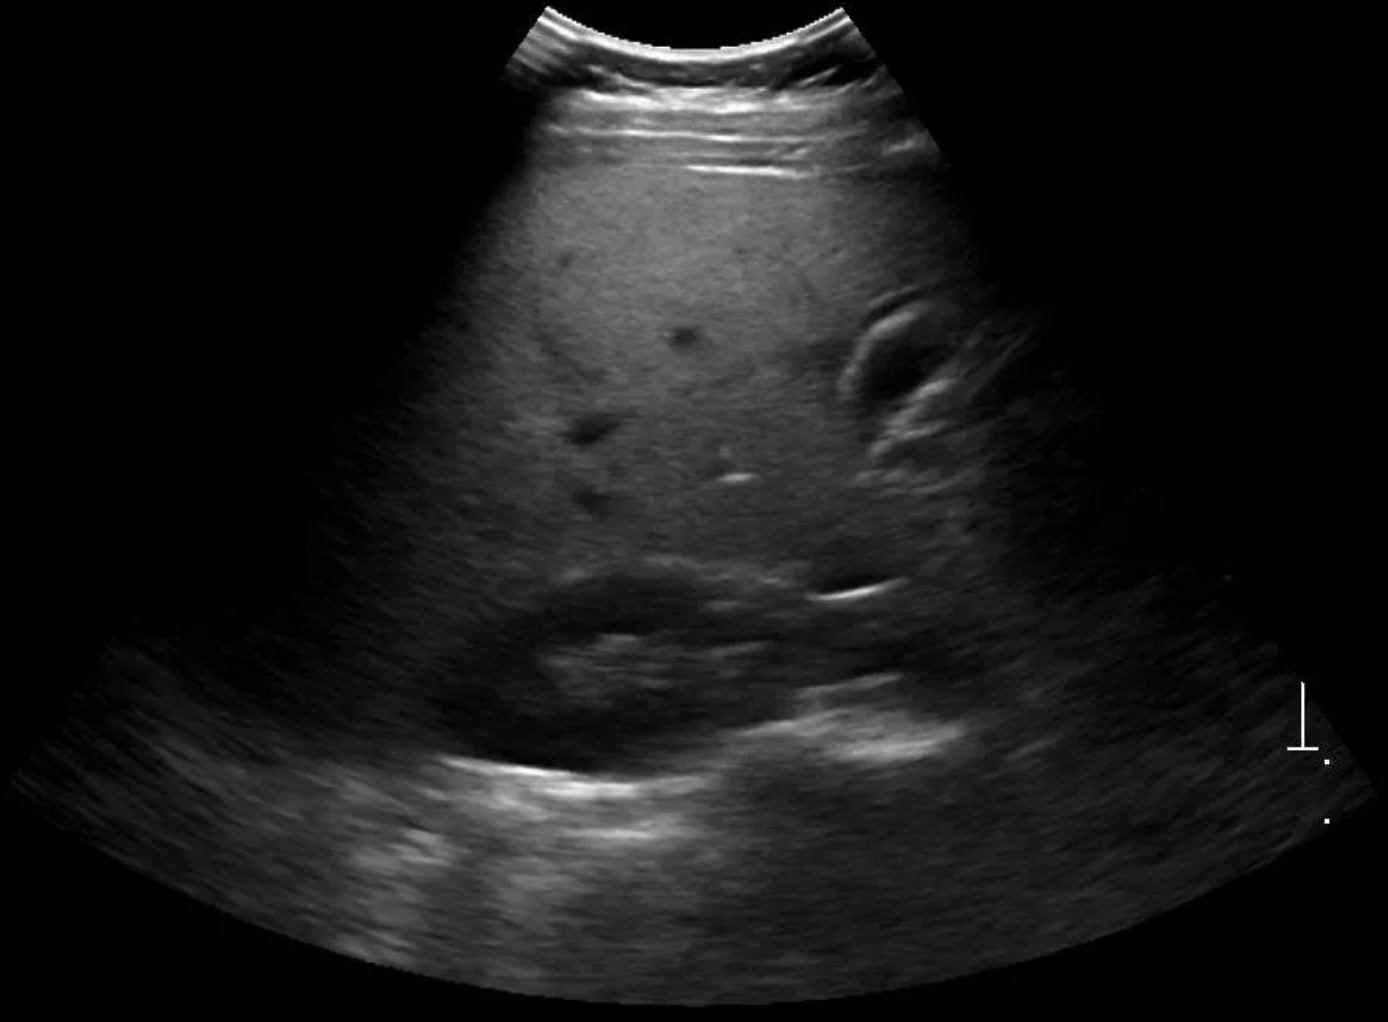

Fatty-Liver Diagnosis

Differentiating fatty liver from non-fatty liver using AI and widely available ultrasound.

Focused on differentiating fatty liver from non-fatty liver by teaching AI to learn Liver Steatosis and Fibrosis scores from normal ultrasound images. The objective is to replicate the expensive "Gold Standard" Fibroscan results using widely available, cheaper ultrasound machines.

Impact

The project aims to achieve accuracy similar to Fibroscan while drastically reducing the cost of testing from ₹3,000–₹10,000 to approximately ₹600–₹800 per test, expanding access to millions.